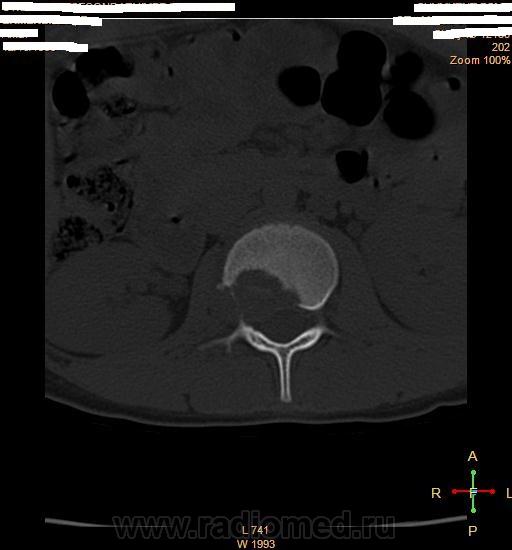

Здравствуйте коллеги.Прошу ваши помощи больной 1998 г.р. беспокоять боль поясничной области справа.Болеет в теч месяца, связывает с резким движением.Лечились по поводу почки без эфекта. Анализ не здали.Травму исключает. МРТ от 21 .10.2013 г. МР признаки участка патологич. измен. сигнальных характеристок с перифокальным трабекулярным отеком в теле и правой дужке позвон L2.Паравертабр. мягкотканный компонент в правой корешковой воронки на уровне L2-3.Этиология?Не исключается наличие осложненной переломы гемангиомы тела L2.Дифференцировать специфическим спондилитом .Анатомически суженный спинно- мозговой канал. Со слов матери костные фтизиатры исключили свое.Ваше мнение.

Образование позвонка, дифряд - ГКО, остеобластома, агрессивная гемангиома, солидный вариант АКК.

Транспедикулярная биопсия